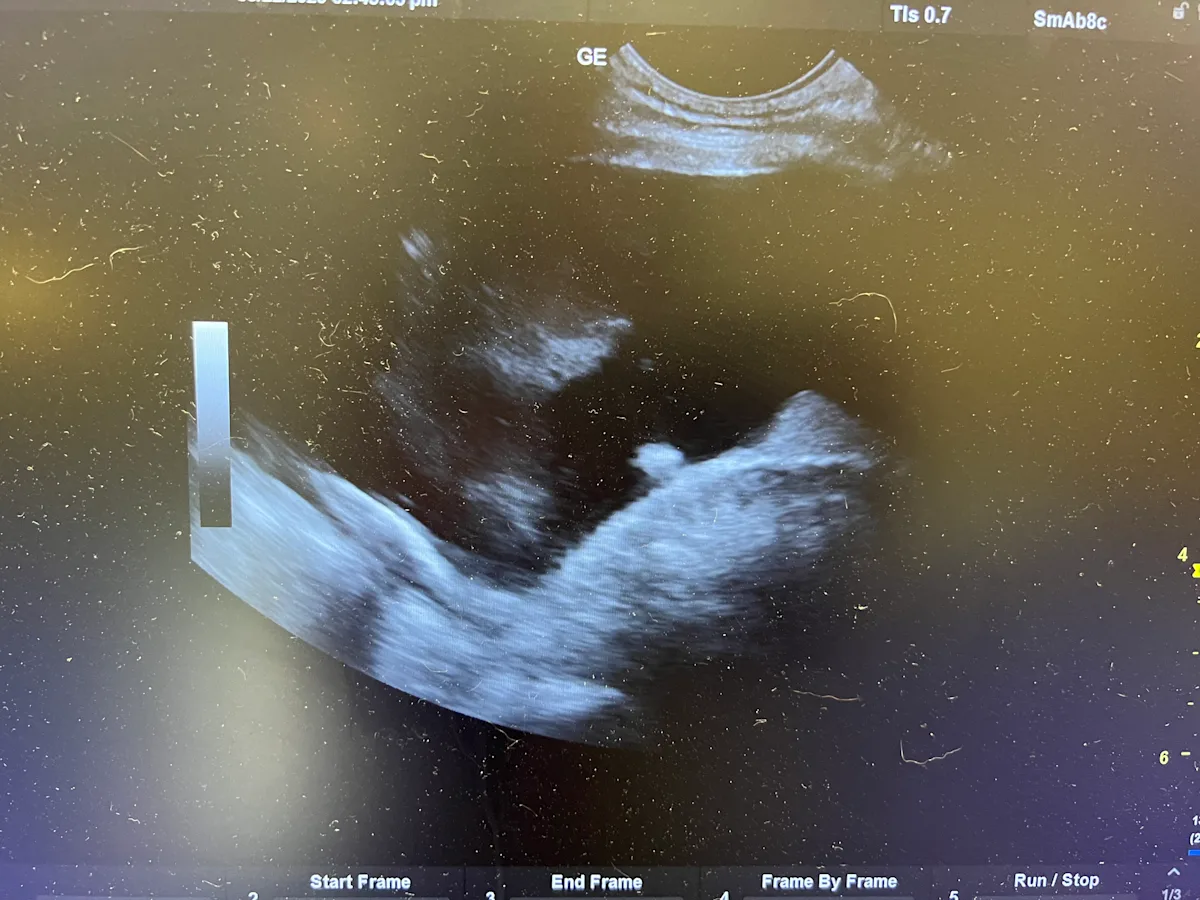

On ultrasound, pleural effusion appears as an anechoic pocket separating the lung lobes from the thoracic wall.